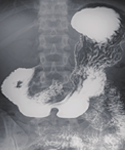

● 高清透视

在初诊筛查的基础上,使用高清透视功能辅助医生再次确认病灶点,降低漏诊、误诊的概率。

● 高清点片

在透视检查下,可进行毫秒级高清点片,准确捕捉病灶,为医生提供高清的诊断依据。